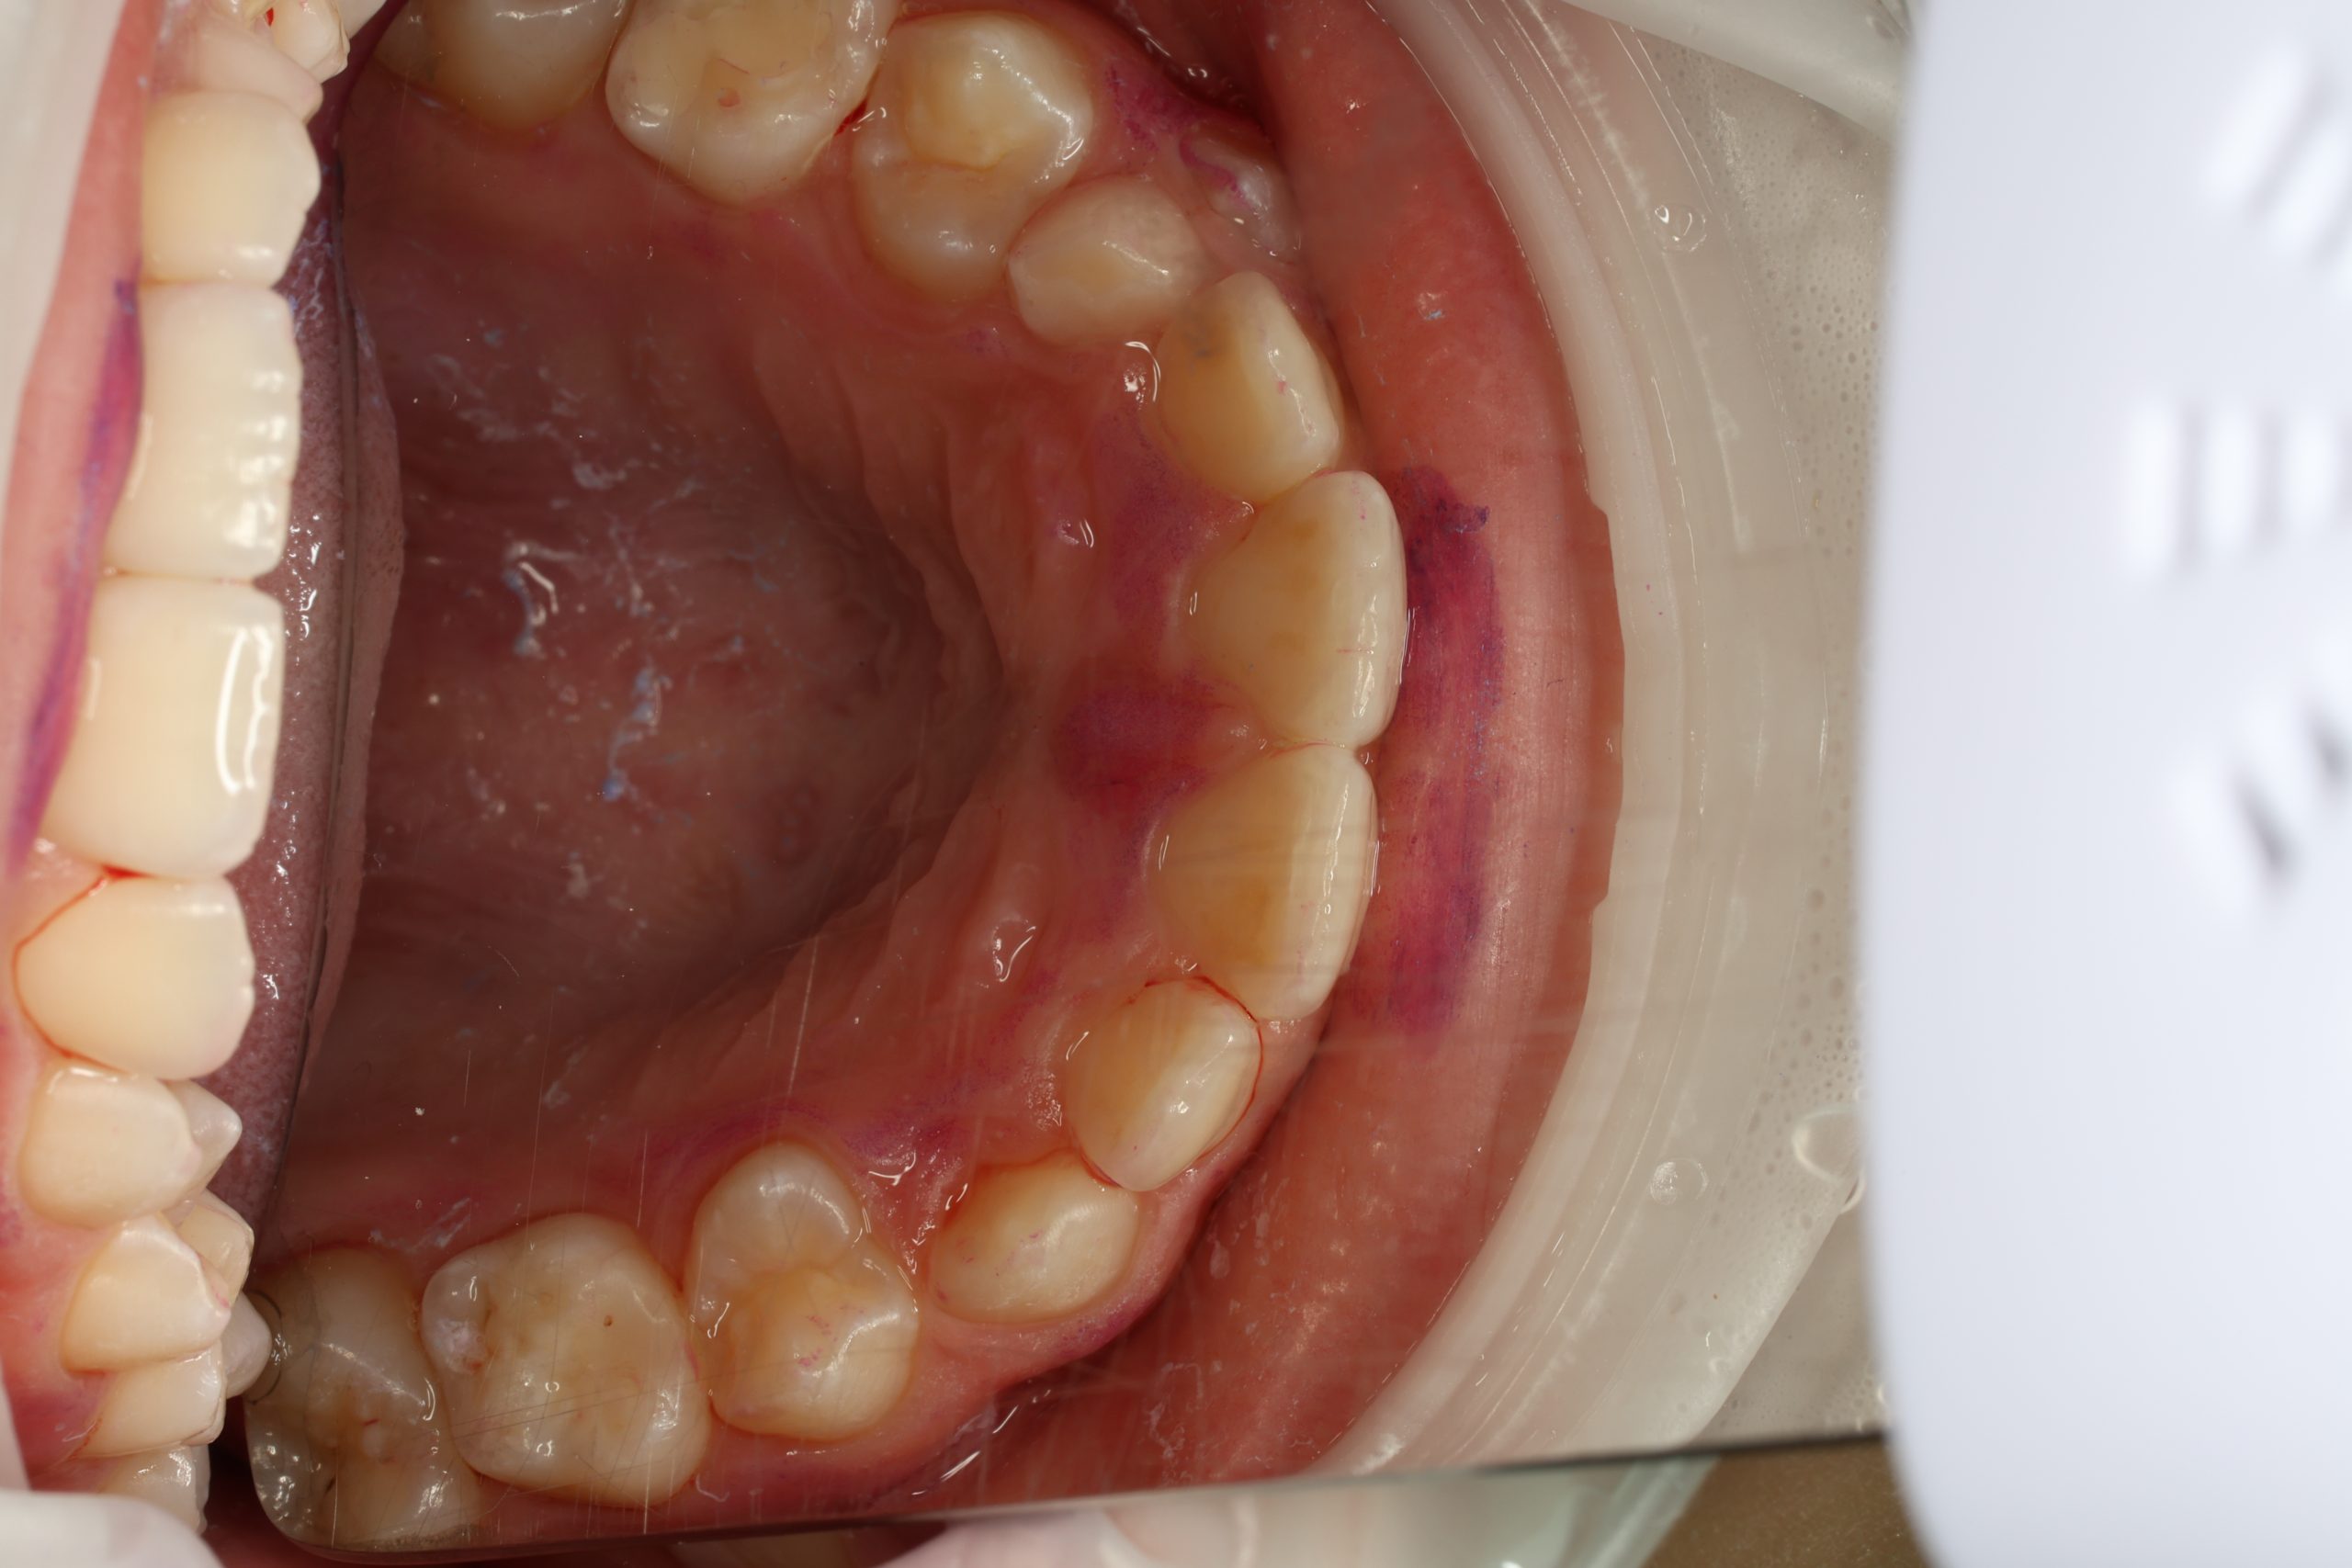

We examine the condition of teeth, gums, and bite. - Plaque Disclosure with Special Indicators

Areas that weren’t cleaned well appear purple. The darker the shade, the older the plaque. This helps both kids and parents understand where brushing needs to improve. - Brushing Training & Home Care Tools Selection